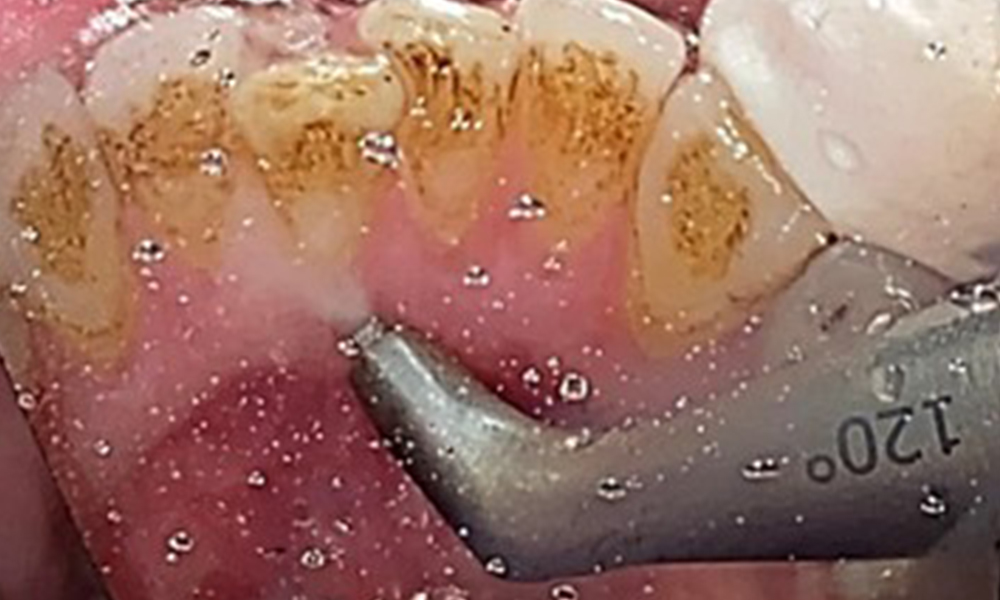

Close-up view of teeth

Fig. 5: Close-up view of teeth 45 to 47. The green arrows show dental attrition and erosions of the buccal cusps with partial enamel loss, © Dr R. Krapf

The objective would be to control disease risk by removing supragingival and subgingival biofilm. The instruments can be selected based on patient needs. First, calculus and any concretions must be removed using ultrasonic and/or manual instruments (Fig. 10).

Use of a piezo-driven ultrasonic device in the lingual area near 36 (Proxeo Ultra, W&H, shown here)

Fig. 10 Use of a piezo-driven ultrasonic device in the lingual area near 36 (Proxeo Ultra, W&H, shown here), © Dr R. Krapf